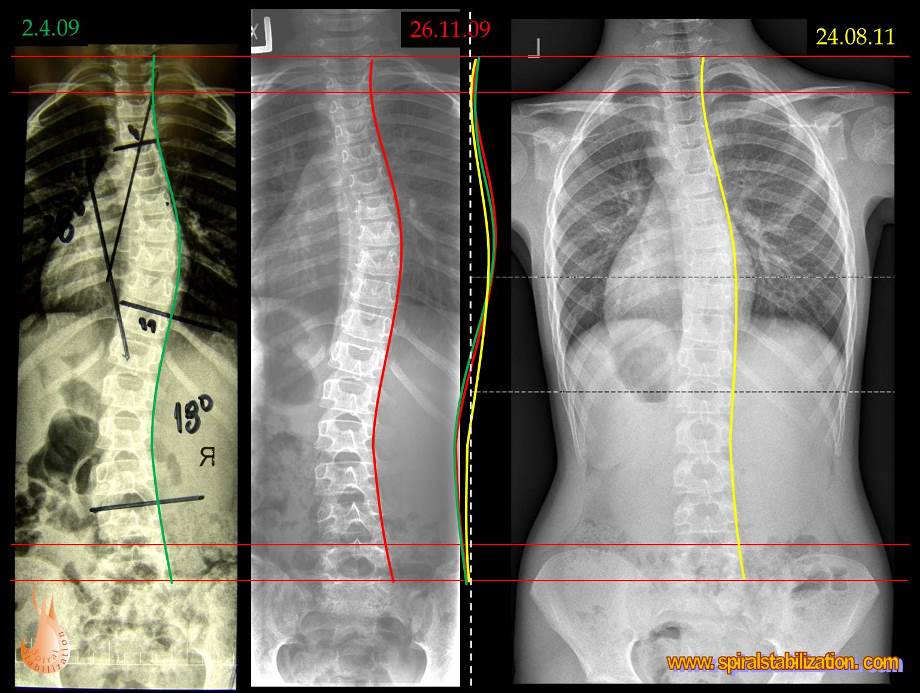

Skoliózu môžeme charakterizovať ako trojrozmernú deformitu so sklonom a posunom stavcov vo frontálnej (stranové zakrivenie), sagitálnej (zmeny fyziologickej lordózy a kyfózy) a tranzverzálnej (rotácia chrbticového stĺpca) rovine. Jednoducho povedané, je to chorobné vykrivenie chrbtice mimo jej prirodzenú krivku.

Veľkosť deformity sa hodnotí vo všetkých troch rovinách. Metódou podľa Cobba možno odčítať uhlovej zakrivenie v predozadnej projekcii (AP = Antero-posterior) a v bočnej projekcii (sagitálnej rovine). Modernými zobrazovacími metódami možno navyše v osovom reze trupu (v transversálnej rovine) odčítať rotáciu chrbtice.